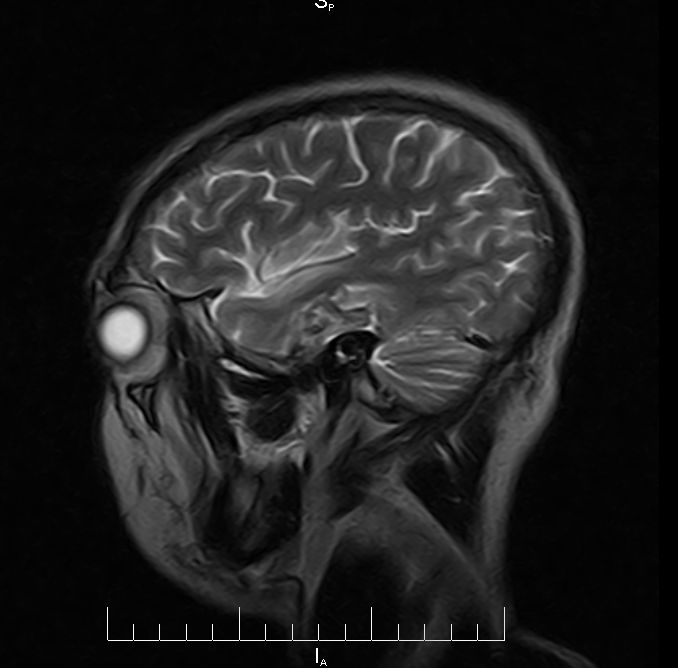

标题: MRI2379:30岁,男,癫痫10年,请各位看一下;CT示:左颞叶钙 [打印本页]

标题: MRI2379:30岁,男,癫痫10年,请各位看一下;CT示:左颞叶钙

考虑左侧颞叶脑血管畸形(avm)。----t1低等高混杂信号,t2等高信号周边较多流空血管影[冠状位明显],mra左侧大脑中动脉受压,远侧聚集.

左侧颞叶占位性病变,室官膜瘤?